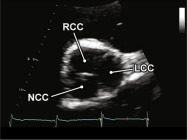

|

||||||||

|

|

Cửa sổ siêu âm cạnh ức

Mặt cắt trục ngắn cạnh ức Phóng đại hình ảnh van động mạch chủ để đánh giá các lá van |

Lá không vành (LCC) Lá vành phải (RCC) Lá vành trái (LCC) |

|||||